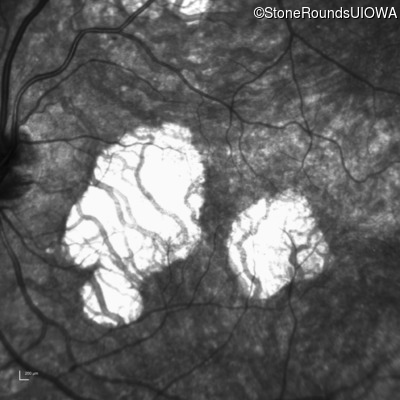

Infrared Fundus Photograph - Left - 20/60 +2 sc

Exemplar